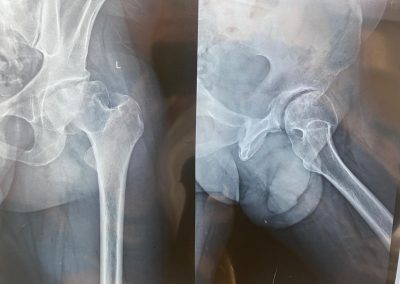

10

حسام الدين عبدالجليل

٣٠ عاما

يعاني من تاكل شديد منذ الطفولة في مفصل الحوض الأيسر.